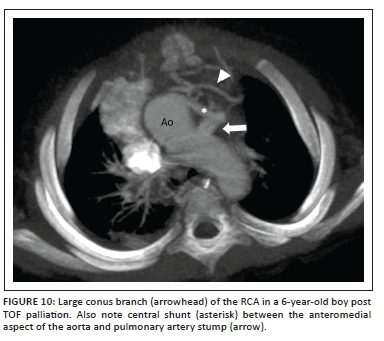

Single or double enlarged conus arteries that take origin from the RCA (Figure 10) and a RCA that arises from the LCA, are further common anomalies that can present a serious hazard at the time of surgery.

Surgical repair can be successfully contemplated even in the presence of a major coronary artery anomaly, provided that the surgeon is made aware thereof. In most instances, proximal coronary anatomy is effectively and reliably demonstrated at echocardiography15 except in instances of previous palliation, late TOF repair or reoperation resulting in a suboptimal acoustic window, or where the coronary arteries pursue an intramyocardial course.

Cardiac CTA, when ECG synchronised (see section above entitled 'Cardiac CTA protocols'), is an alternative non-invasive modality of high diagnostic performance and accuracy, to demonstrate coronary artery origins, their course and spatial relationships to adjoining structures.